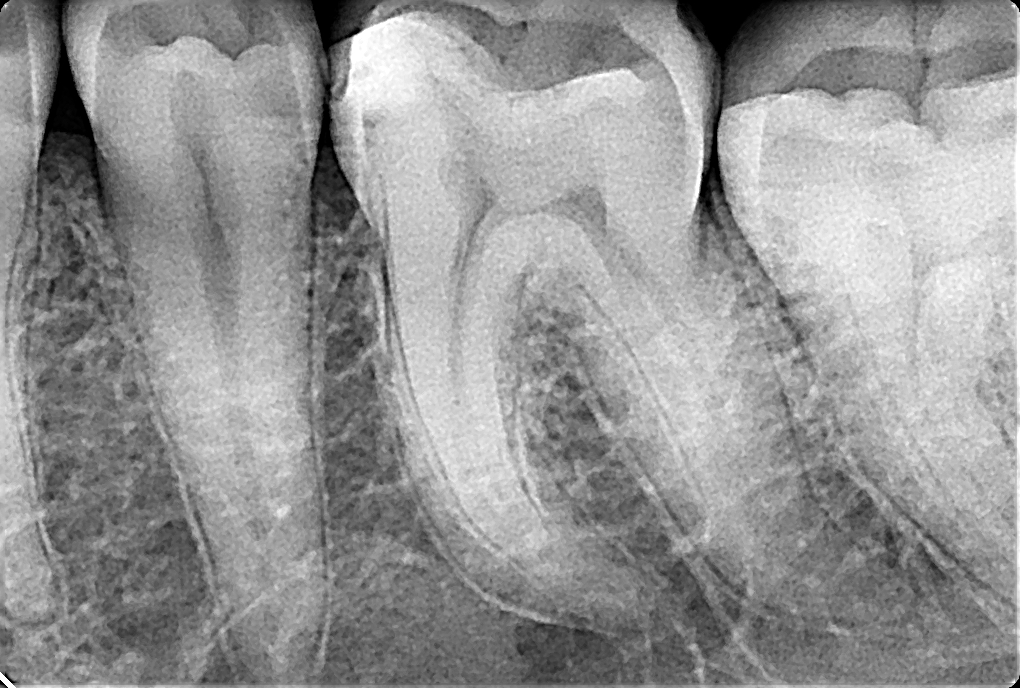

Чаще всего в практике врача стоматолога требуется прицельный снимок. Развитие новейших технологий достигло того уровня, когда интраоральный снимок может быть сделан с минимальной лучевой нагрузкой. В стоматологии Tomchuk Dental Clinic вы можете воспользоваться цифровым рентген аппаратом, и сэкономить свое время, увидев результат сразу на мониторе компьютера. При съемке мы используем технику прямого угла. Этот метод намного более точен, а также удобен для пациента. Доза облучения, получаемая пациентом в этом исследовании, является одной из самых маленьких в радиологии.

Этот тип рентгена используется:

- при поиске причины зубной боли

- при проведении дифференциальной диагностики кариозных поражений зубов и их осложнений

- в оценке на этапах лечения, контроля и качества заполнения каналов